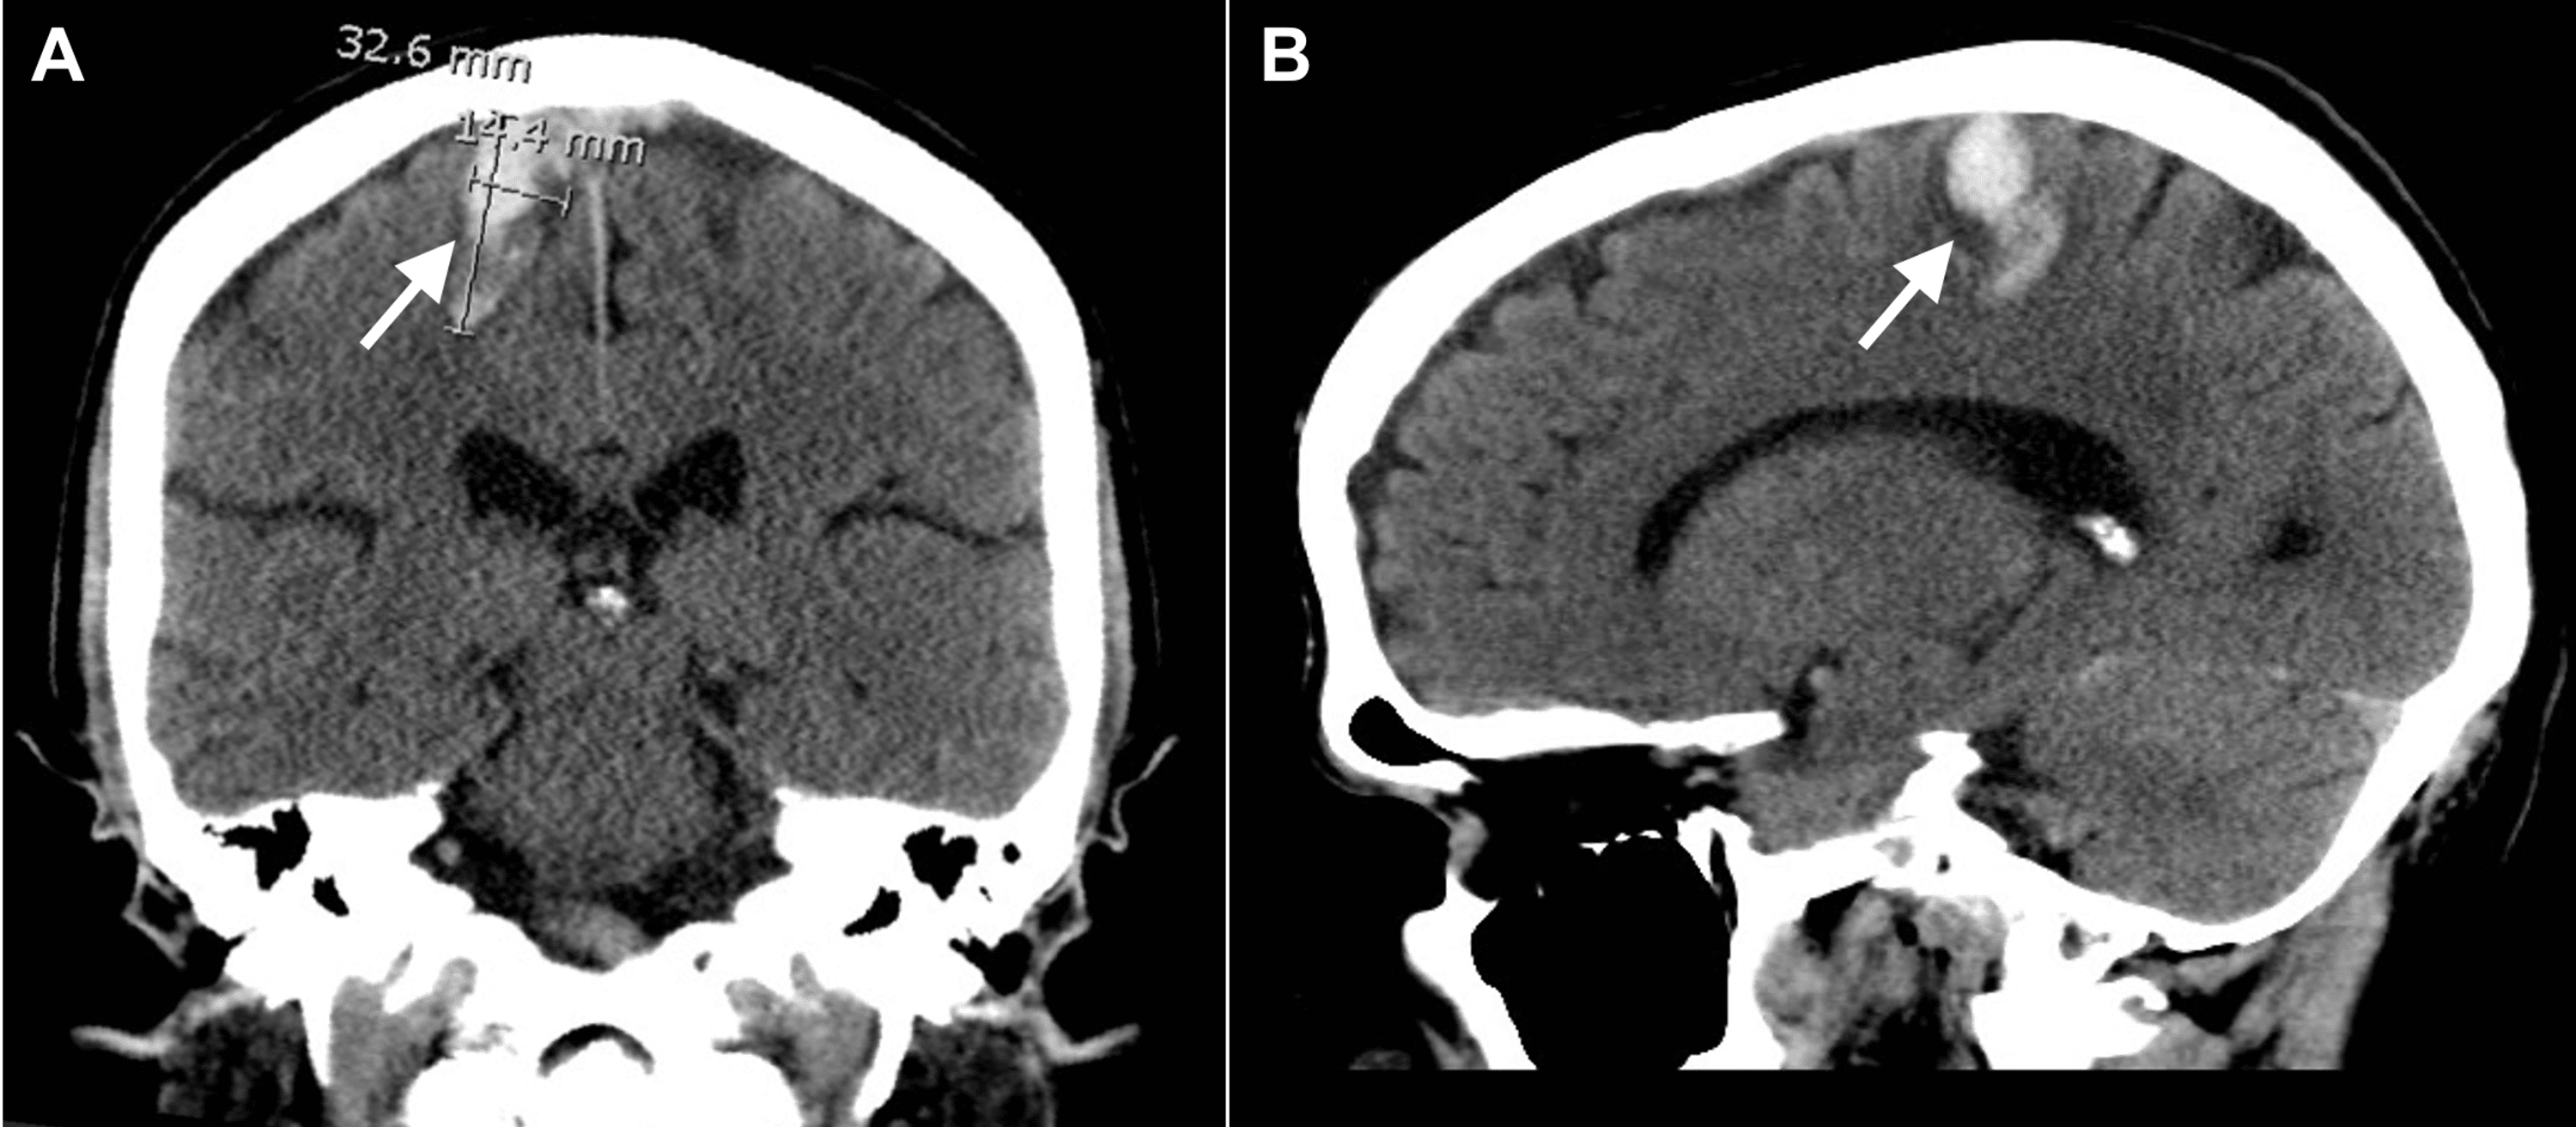

Isolated Lower Limb Weakness Following Hemorrhagic Stroke A Case Isolated Lower Limb Weakness This article describes a case from the emergency department of left lower limb. The differential diagnosis of muscle weakness in adults is extensive because it can occur when pathology affects any level of the neuromuscular pathway (upper or lower motor neurons,. Sudden weakness, numbness, and severe pain localized to a limb are more likely caused by local arterial occlusion and. Isolated Lower Limb Weakness.

Isolated Lower Limb Weakness Following Hemorrhagic Stroke A Case Isolated Lower Limb Weakness Proximal myopathy presents as generalized muscle weakness commonly involving the muscles of upper and/or lower limbs. This article describes a case from the emergency department of left lower limb. Sudden weakness, numbness, and severe pain localized to a limb are more likely caused by local arterial occlusion and limb ischemia, which can. The approach to the diagnosis and initial management. Isolated Lower Limb Weakness.

[PDF] Isolated Lower Limb Weakness Following Hemorrhagic Stroke A Case Isolated Lower Limb Weakness The approach to the diagnosis and initial management of patients presenting to the ed with acute, nontraumatic neurologic and. Peripheral neuropathy, a common neurologic problem encountered by family physicians, can be classified clinically by the anatomic pattern of. The differential diagnosis of muscle weakness in adults is extensive because it can occur when pathology affects any level of the neuromuscular. Isolated Lower Limb Weakness.